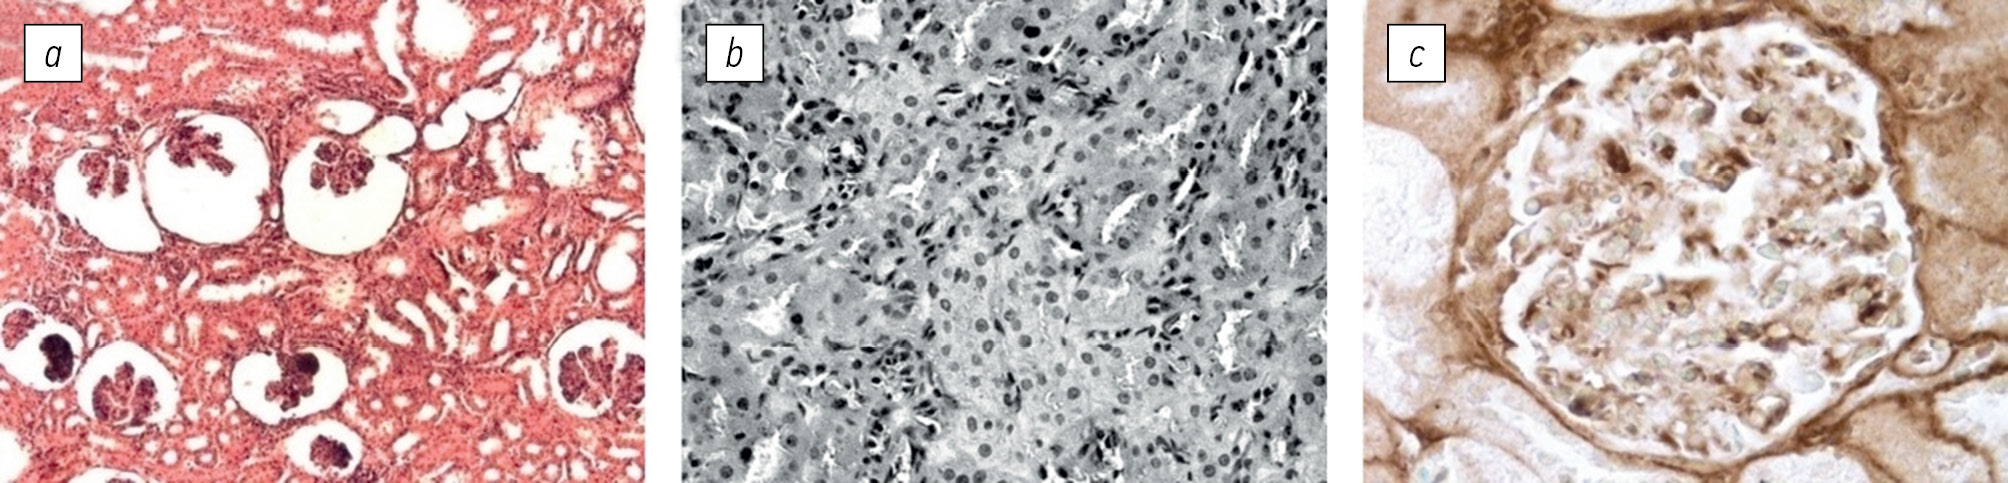

Fig. 3. Morphological changes in cortex and medullar substances of the rabbit renal tissue induced by Streptococcus pyogenes of genotype emm1 [82]: a — the capsular cavities of the glomeruli strongly expanded, in the capillary loops of the glomeruli necrosis and atrophy are observed, in the wall of the proximal tubules of the cortex desquamation of epithelial cells is revealed (shown by arrows); b — swelling and thickening of the membranes of the wall of distal tubules in the medulla with the simultaneous proliferation of the fibrous interstitial tissue; c, d — absence of pathological changes in the cortex and the medulla of the kidney obtained from rabbits treated with Fc fragments of IgG. Staining with hematoxylin-eosin, ×750

It has been demonstrated that the early introduction of human or rabbit purified Fc fragments of IgG to experimental animals in the early stages of glomerulonephritis development can prevent or reduce the severity of the disease [82, 83]. The process was initiated by GAS type M1 (Table 3; Fig. 3). There are two potential mechanisms for suppressing the disease in the renal tissue:

- Fc fragments of IgG interfere with the IgGFc-binding activity of the injected bacteria, preventing the formation of autoantigens and reducing the production of anti-IgG autoantibodies;

- Fc fragments of IgG block tissue Fcγ-receptors, inhibiting immune inflammation and reducing the expression of inflammatory mediators.